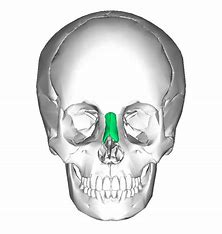

Nasal bone

Perpendicular plate of the ethmoid bone (helps form bony nasal septum with vomer)